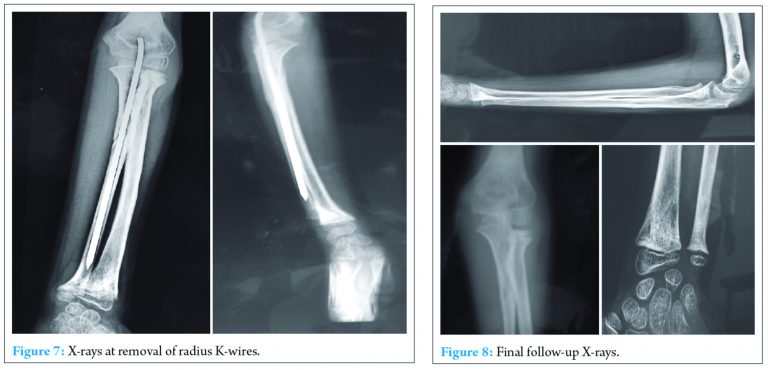

Elbow range of motion was started at 6 weeks along with pronation and supination. X-rays showed union at this stage in all the fractures. Ulna K-wire was removed at 12 weeks. At final follow-up at 6 months, fractures were consolidated (Fig.7) with near normal range of motion (Fig. 8-10). Patient’s father was advised regular follow-up of child, as premature closure of physis is expected secondary to epiphyseal separation, as noticed in the final follow-up X-rays of the distal radius.